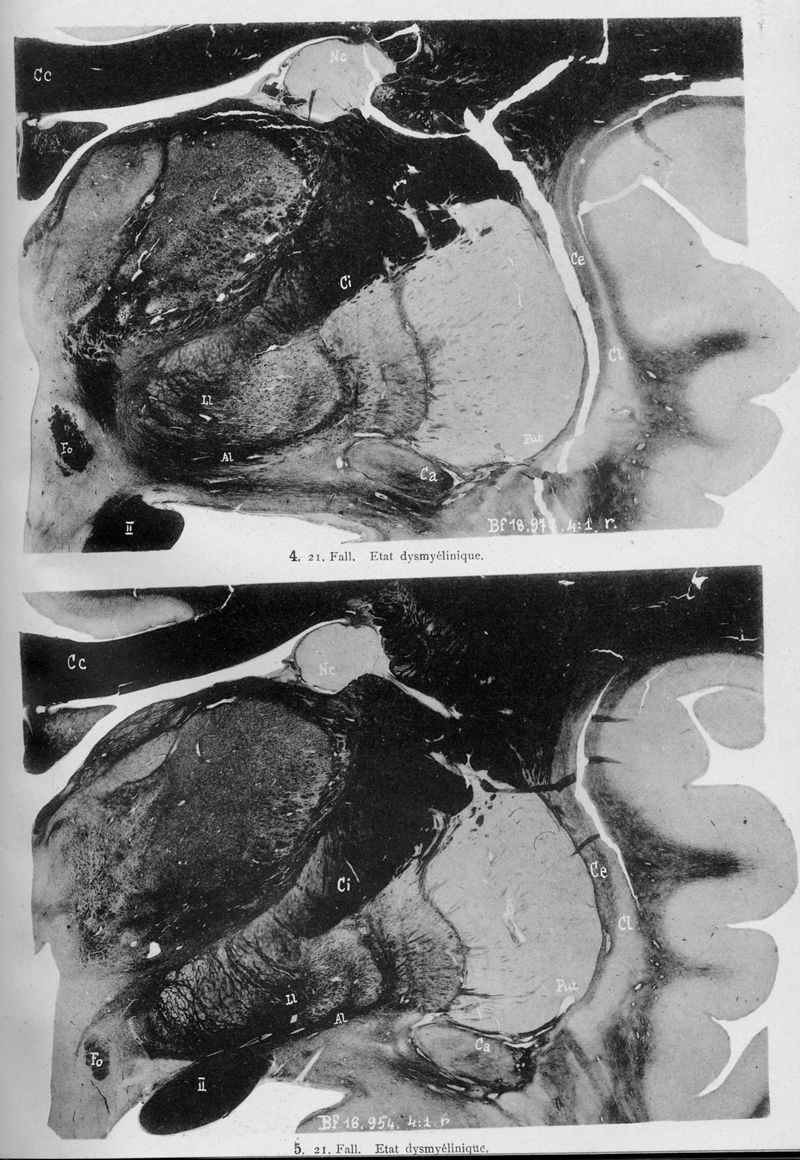

VOGT, Cécile / VOGT, O.

In : Journal für Psychologie und Neurologie,

1920, Vol. 25, pp. 627-846